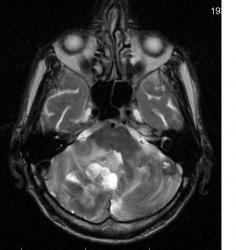

Мужчина 73 лет. За последний год похудел, потерял аппетит. Последний месяц стал плохо ходить, несколько раз падал, неделю назад стал психически не совсем адекватен. Врач - друг семьи, приехавший в гости, настоял на проведении МРТ головного мозга, рентгенографии ОГК и УЗИ брюшной полости. МРТ проводилось в медикаментозном сне, с реанимационным набором наизготовку, по немного укороченным программам. Все закончилось благополучно. Ничего сложного в плане диагностики. Просто не всегда бывает так много и ярко. Есть небольшое продолжение. Потом.

Т2 ВИ аксиальные сканы:

метастазы